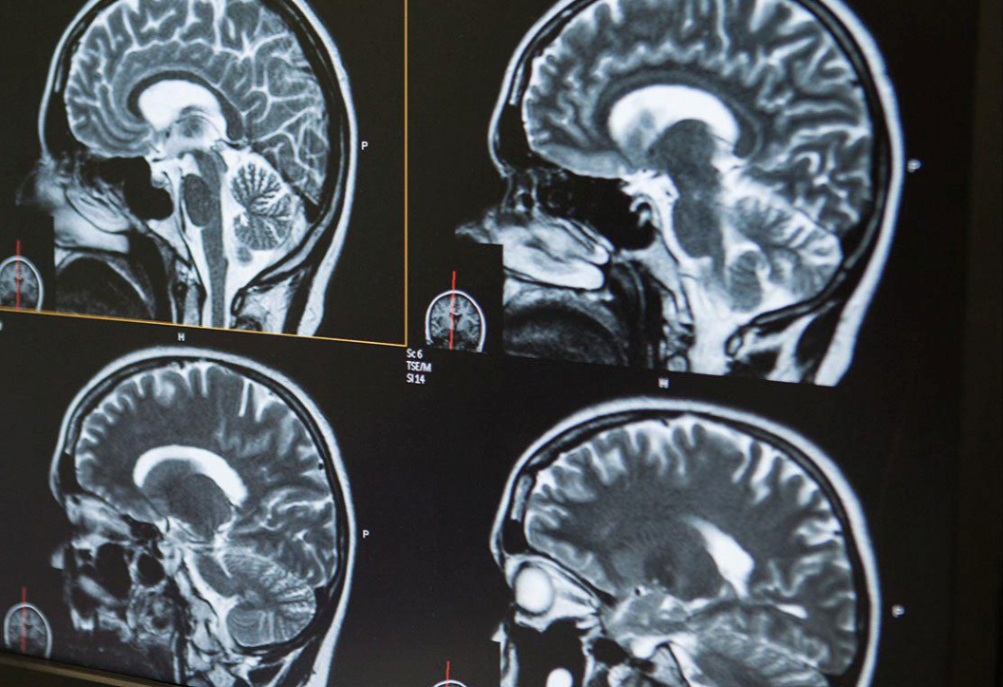

Магнитно-резонансная (МР) трактография мозга

Магнитно-резонансная трактография — это высокотехнологичный метод визуализации белого вещества, позволяющий отследить структуру и направление нервных волокон. Метод основан на диффузионно-тензорной томографии (DTI), разновидности МРТ, при которой измеряется движение молекул воды вдоль аксонов. Результатом становится трехмерная реконструкция проводящих путей, которая помогает оценить их анатомию, непрерывность и возможные повреждения.

В отличие от стандартного МРТ головного мозга, трактография отображает не только строение, но и «связи» внутри мозга, визуализируя информационные пути между его участками.

• Процедура проходит в МРТ-кабинете на аппарате мощностью не менее 1,5 Тесла (в идеале — 3 Тесла). Пациент размещается в аппарате, как при обычном МРТ головного мозга. Исследование занимает 30–45 минут, все это время важно лежать неподвижно.

• Для трактографии используются специальные последовательности, позволяющие зафиксировать направление диффузии молекул воды в ткани мозга. Изображения обрабатываются на отдельной рабочей станции, где врач-радиолог строит карту трактов, оценивает их симметрию, непрерывность и целостность.